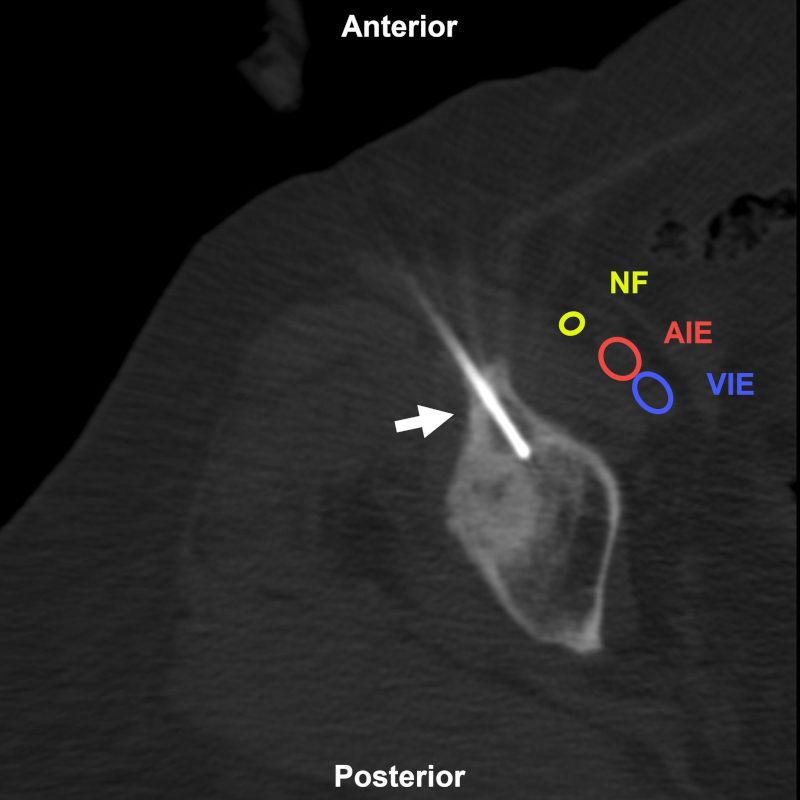

Mujer de 76 años con antecedentes de cáncer de mama con imagen lítica periacetabular derecha. BP con abordaje directo anterolateral (flecha). Estructuras a evitar: AIE: arteria ilíaca externa; VIE: vena ilíaca externa; NF: nervio femoral. Aguja utilizada: Jamshidi 11 G. Diagnóstico final: cambios reparativos.

Figura 11